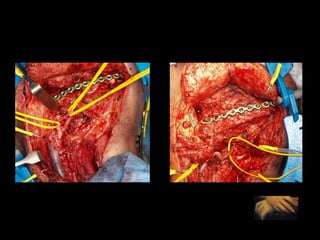

Moldeado previo de la placa

Relación céntrica Sistema de fijación

Mejor planificación estética Y funcional mandibular en el auto trasplante de tejidos. Disminución del tiempo quirúrgico en el modelado de la placa mandibular 60´. Mantenimiento de la relación céntrica. Mayor exactitud con la “técnica en espejo”.

Evitar contaminación de campos. Mayor eficiencia al planificar y realizar las osteotomías mandibulares. Mayor eficiencia al planificar y realizar las osteotomías del peroné.